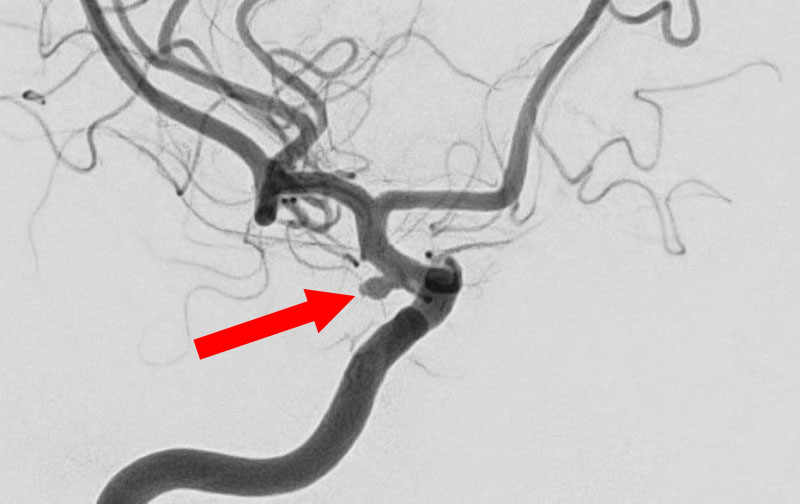

No.1618 手術前